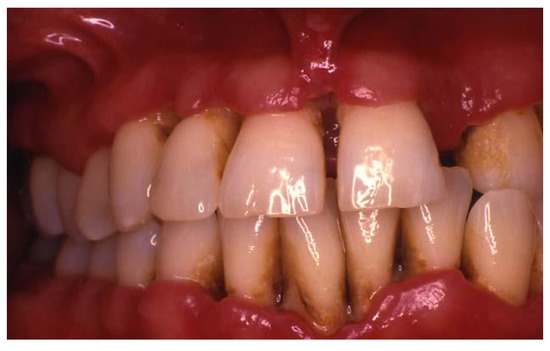

2.2. Necrotizing Periodontal Diseases (NPDs)

2.3. Periodontitis as a Manifestation of Systemic Diseases

2.3.1. Down Syndrome

2.3.2. Human Immunodeficiency Virus (HIV)

2.3.3. Rheumatoid Arthritis (RA)

2.4. Systemic Diseases or Conditions Affecting the Periodontal Supporting Tissues